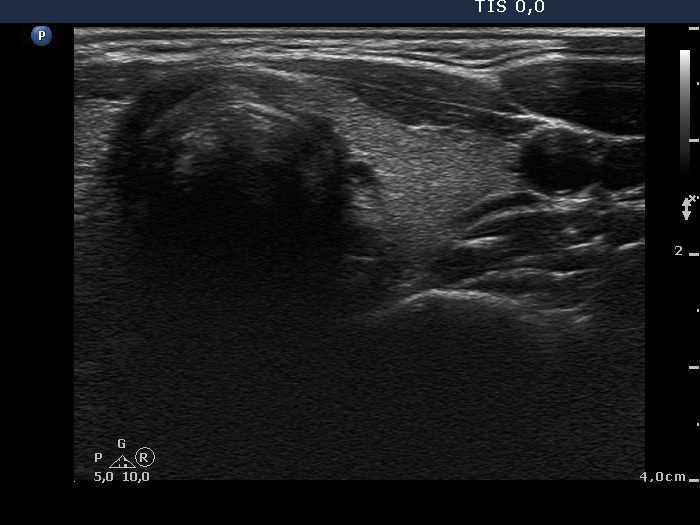

Right lobe, transverse scan

This is the usual course of Graves' disease regarding the change in echo pattern - before, during and after the activity of the autoimmune process. The only exception is the change in the size of the thyroid. In most cases, the thyroid increases during the activity of the disease, then returns to normal. However, in this patient the age counts: at the first examination, the patient was only 15-year-old.